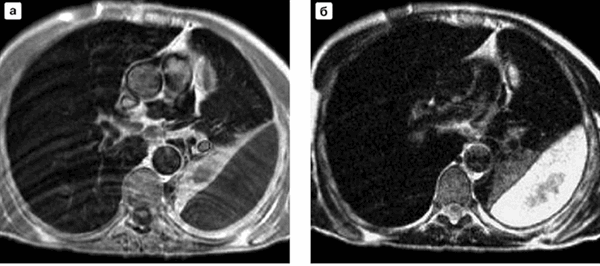

МРТ легких в аксиальной проекции при абсцессе правого легкого (нижняя доля): а - Т1-взвешенное изображение; б - Т2-взвешенное изображение

МР-снимки легких визуализируют:

- скопление жидкости в плевральной полости;

- очаги фиброза;

- новообразования;

- плевриты;

- абсцессы;

- кисты;

- нарушение кровотока в сосудах;

- инфаркт легкого и др.